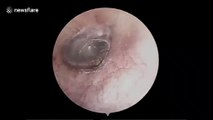

Stomach-churning footage shows twitching mosquito deep inside man's nose

A mosquito was discovered living in a man's nose in Vietnam.

The man had visited the doctor in Hai Duong City in northern Vietnam,

reporting a strange sound in his nose accompanied by an itchy sensation.